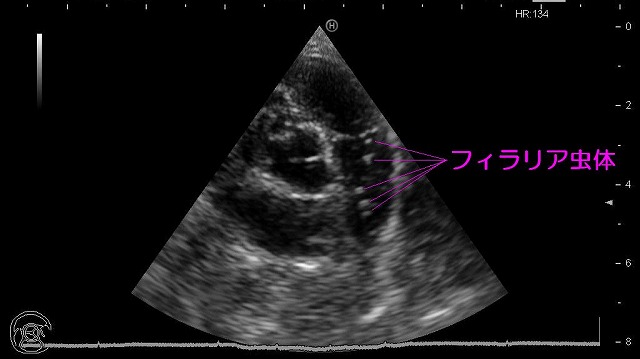

特に心臓のエコー検査はとても大切な検査の一つです。

・弁膜がスムースに開かなくなり血液の流れが悪くなっていないか?

・弁膜がすきまなく閉じなくなり血液が逆流していないか?

・心臓の周りに液体が溜まって心臓の動きが悪くなっていないか?

・心臓に出来物が出来ていないか?

などの様々な情報を得ることが出来ます。